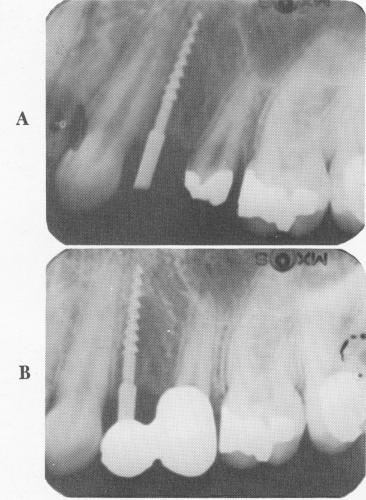

Fig. 8-69. A, An intraoral radiograph showing the narrow ridge implant in the bone to its desired depth. B, The x-ray shows the prosthesis cemented over the implant and tooth abutment.

The two-unit, prefabricated splint was fitted over the implant shaft and prepared bicuspid tooth (Fig. 8-67). (If any interference occurs from such a post, a larger hole can be made on the under-surface of the abutment crown.) The bridge was then cemented into position with a hard cement (Fig. 8-68). During this procedure, as should be done during all implant interventions, x-rays were taken as guides (Fig. 8-69).